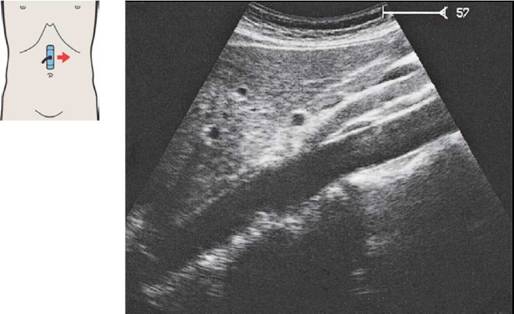

Печень при продольном сканировании

57 Левая доля печени, латеральный сегмент, II и III субсегменты

По анатомическим критериям в печени выделяют левую и правую доли. Левой доле соответствует латеральный сегмент; правая доля состоит из медиального, переднего и заднего сегментов.

По функциональным критериям латеральный и медиальный сегменты! относятся к левой доле печени, а передний и задний - к правой.